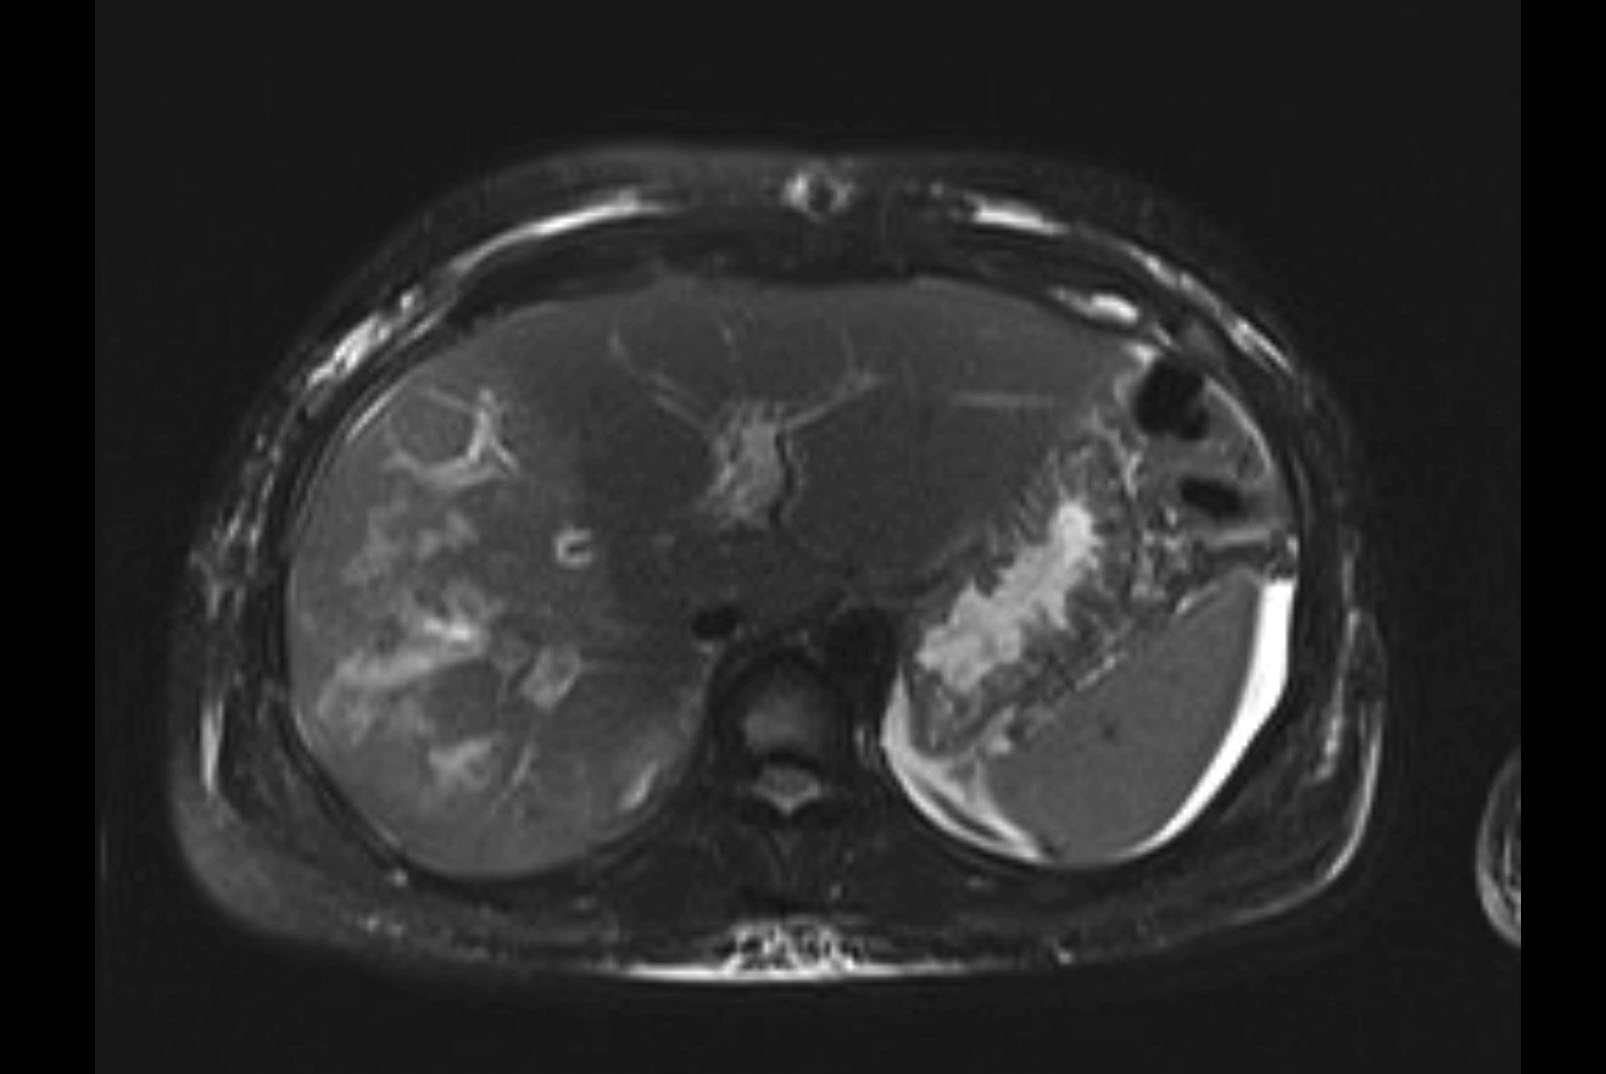

Imaging Analysis

Look through the patient's CT scan to identify any areas of concern for the necessary procedure.

MRI T2

Based on initial findings, which issue(s) would you be most concerned about?